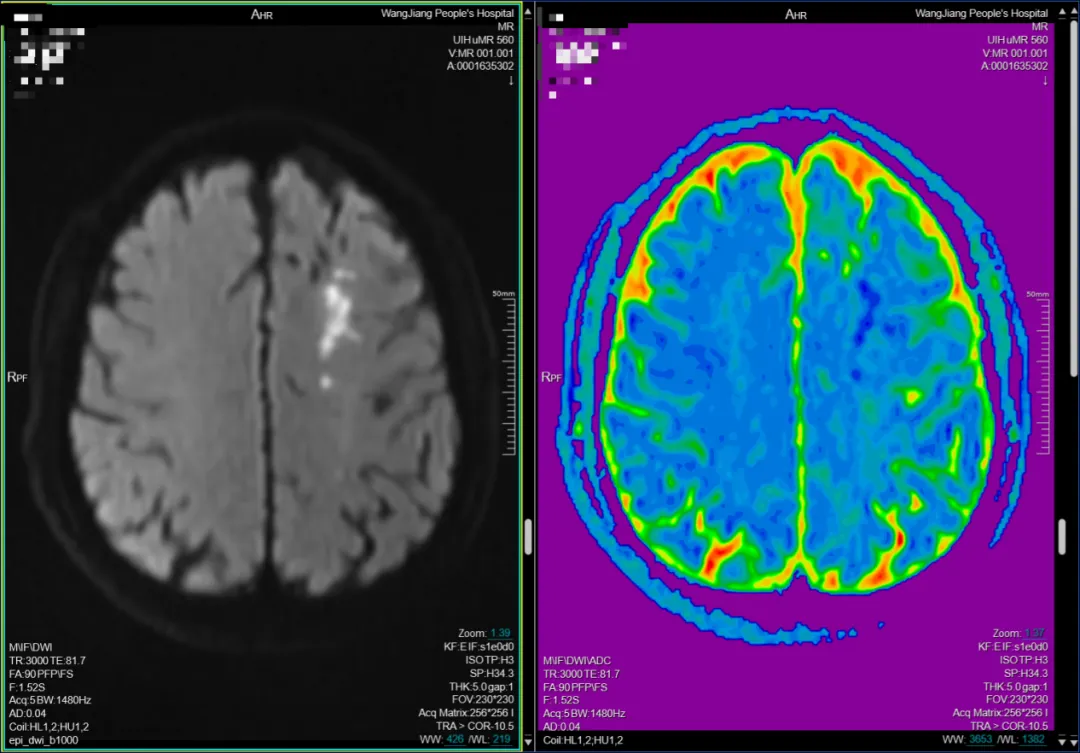

3.多序列MR聯(lián)合診斷:無癥狀腦梗塞與腫瘤的“終結(jié)者”。隱匿性腦梗塞:DWI(彌散加權(quán)成像)可在梗塞后數(shù)分鐘檢出超急性期病灶,而Flair序列擅長發(fā)現(xiàn)陳舊性小梗塞(<5mm),這些“靜默殺手”可能是未來大卒中的前兆。

左側(cè)額葉急性腦梗塞